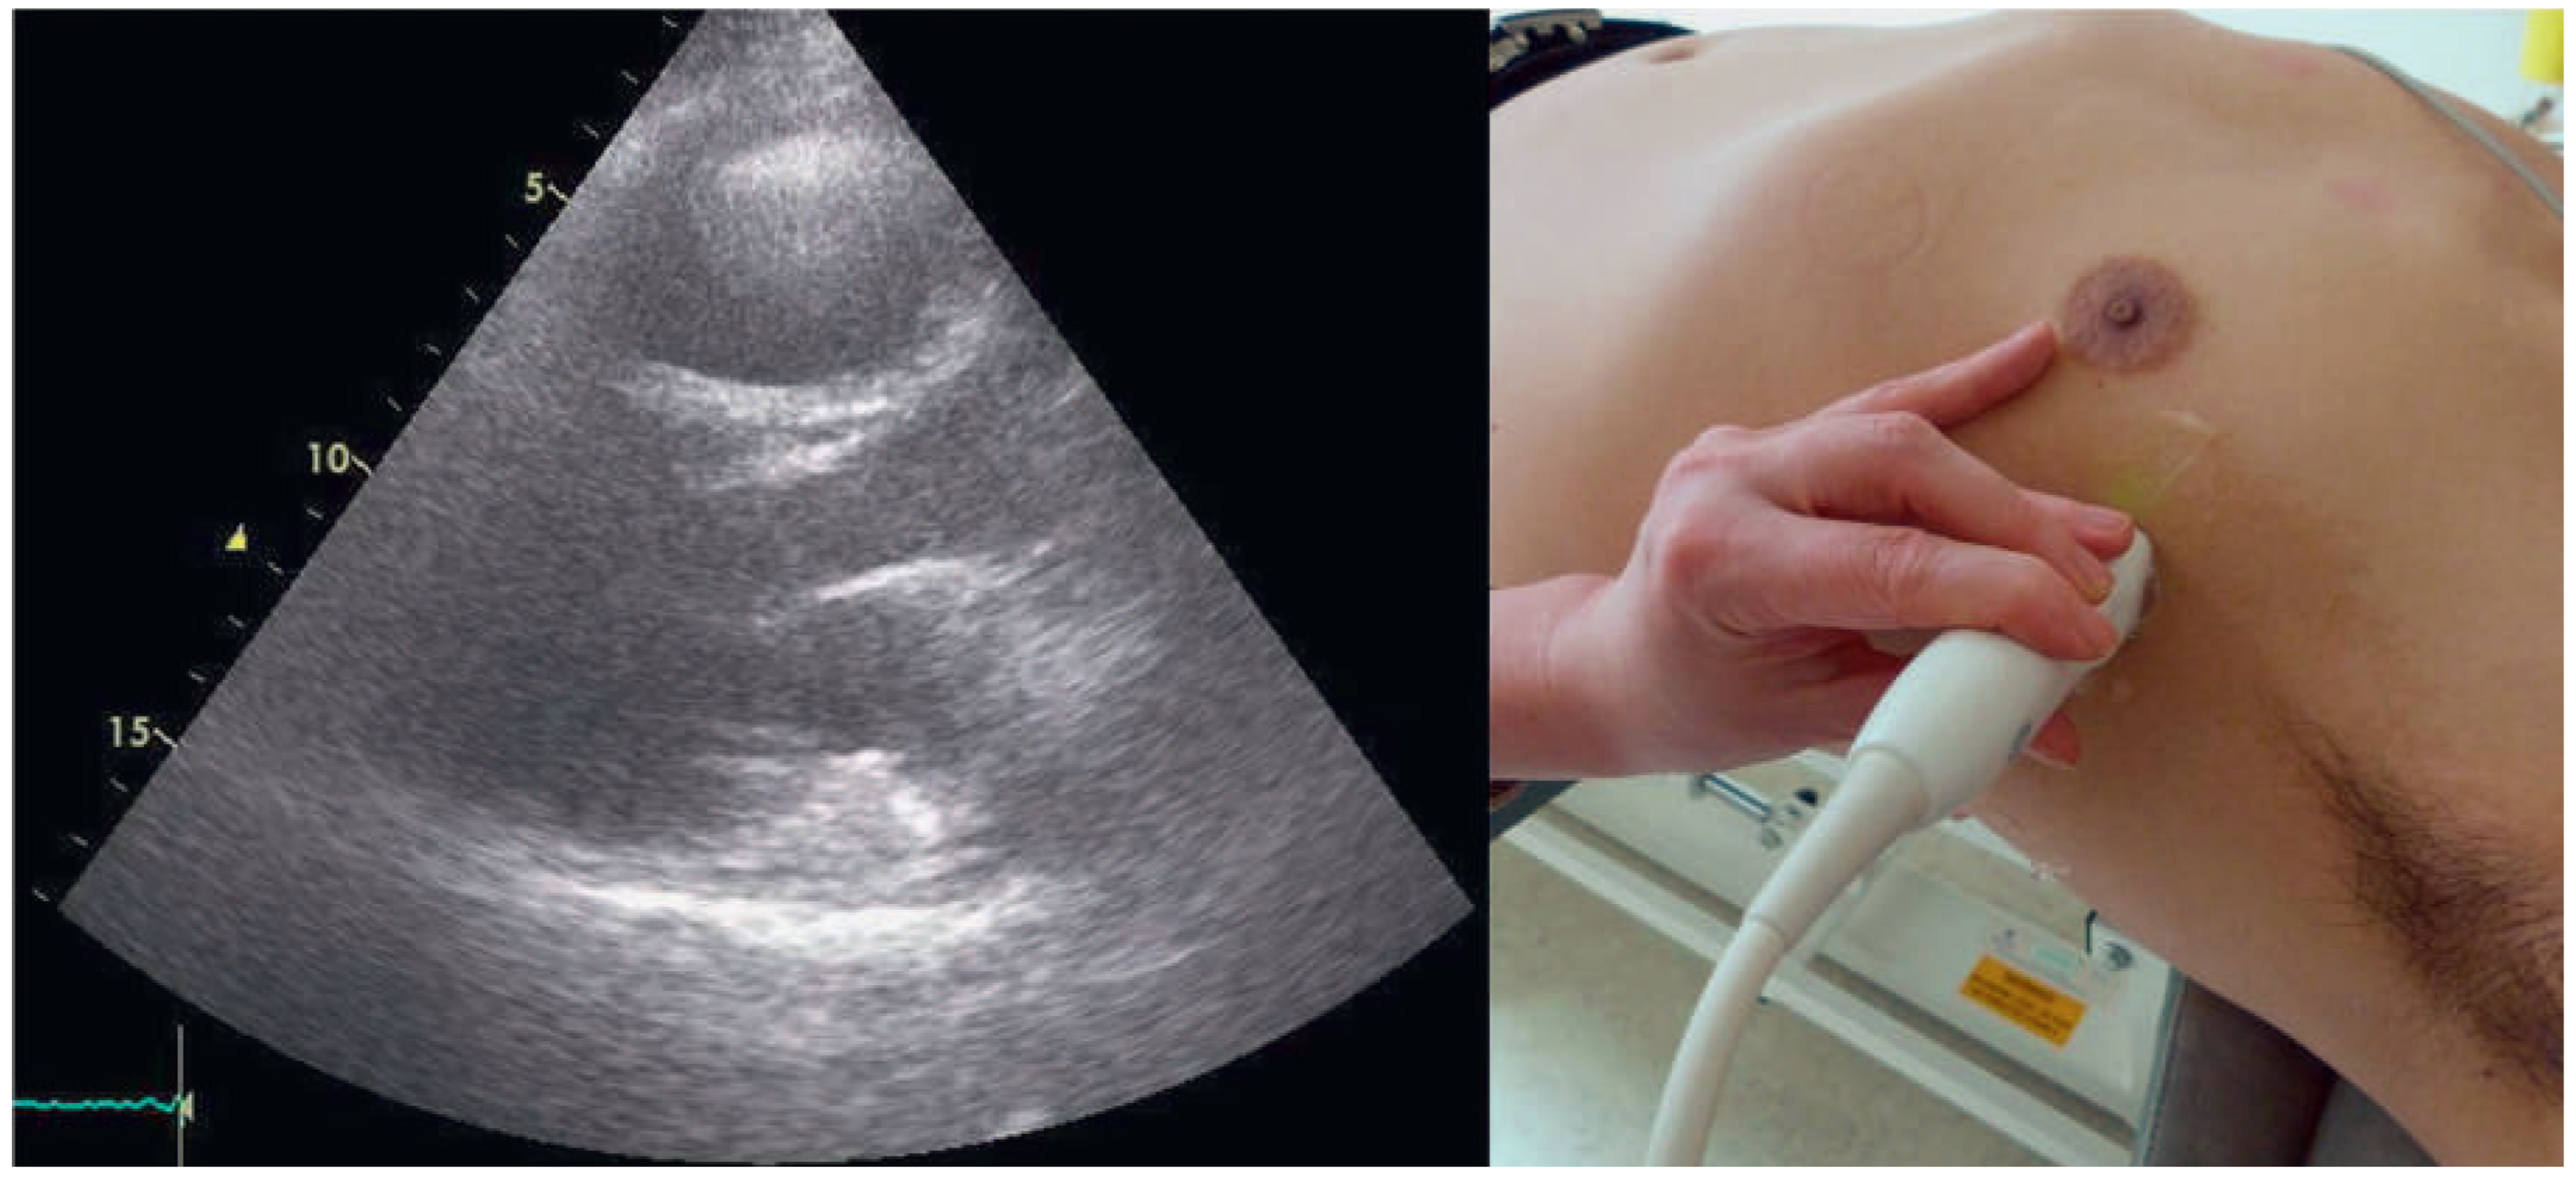

A 57-year-old male presented to the medical outpatient department with typical angina pectoris Canadian Cardiovascular Society (CCS) class II and dyspnoea on exertion during the previous weeks. Additionally he had retrosternal pain at rest and dyspnoea during the previous night. The patient had a a history of untreated arterial hypertension. On initial workup, the patient was in a stable cardiovascular condition with an office blood pressure of 150/88 mm Hg, and the cardiac examination was unremarkable. Blood tests revealed serially negative high-sensitivity troponins. Glycated haemoglobin was 6.4%, consistent with prediabetes, and lowdensity lipoprotein cholesterol was 2.5 mmol/l. An electrocardiogram (ECG) showed sinus rhythm, right axis deviation, signs of an incomplete right bundle-branch block with rR’ morphology in leads V1 to V4, and lateral displacement of the transition zone in the precordial leads, but no signs of acute ischaemia (Figure 1). On echocardiography, the image acquisition was difficult with a typical long axis view acquired in the fifth intercostal space in the midaxillary line (Figure 2) and apical views acquired from a posterolateral window (Figure 3). Computed tomography angiography (CTA) of the heart showed that the entire heart was displaced leftwards into the left hemithorax. Also evident was a lingula of lung tissue interposed between the aorta and the pulmonary artery indicating a congenitally absent pericardium (Figure 4). Additionally, the CT scan revealed coronary artery disease with soft plaques and >70% stenoses of the left anterior descending artery (LAD), the left circumflex artery (50%–70% stenosis) and the first marginal branch (>70% stenosis). Considering the diagnosis of a congenitally absent pericardium, the ECG was repeated, with leads V7–V9, showing a normal R-progression from V4 to V9 (Figure 5). Coronary angiography with primary stenting of a 95%–99% stenosis of the LAD artery and a 75%–95% stenosis of the first marginal branch resulted in complete resolution of symptoms.

Figure 3. Apical four-chamber view derived from a posterolateral window.

Congenitally absent pericardium is a rare condition found in 1/10 000 autopsies with morphological patterns of: total bilateral absence (extremely rare); partial left absence (70%); and partial right absence (17%) [1]. It may be associated with other congenital defects such as atrial septal defects, persistant ductus arteriosus, bicuspid aortic valve or tetralogy of Fallot [2]. Most patients are asymptomatic but absent pericardium may cause paroxysmal, stabbing, nonexertional chest pain. In partial left absence severe complications may be caused by herniation of parts of the heart resulting in shortness of breath, syncope or sudden death [1,2]. On ECG, partial right bundle-branch block is common and displacement of the transition zone in the precordial leads is seen as a result of the displacement of the heart [2]. On transthoracic echocardiography, the standard views are found to be displaced leftwards as is exemplified in Figure 2. The diagnosis is usually established by use of CT or magnetic resonance tomography showing displacement of the heart into the left hemithorax and lung tissue interposed between the aorta and the main pulmonary artery [2]. In symptomatic patients, and especially in patients with risk factors or symptoms of herniation, surgical therapy with pericardioplasty may be performed [1,2]. Our patient was symptom-free after coronary angiography and no treatment due to the congenitally absent pericardium was necessary.